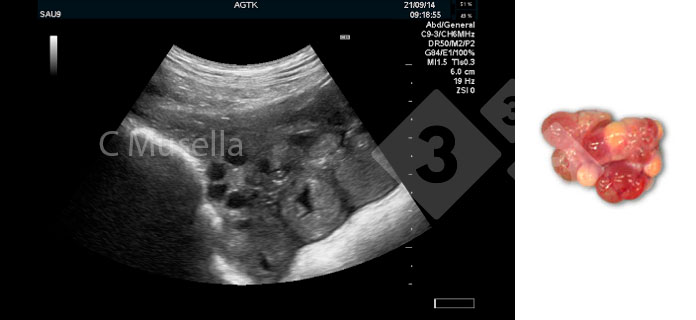

Près de l'ovulation, les follicules préovulatoires passent d'une forme sphérique à une forme ovoïde/polygonale. Le processus ovulatoire peut durer plusieurs heures et des follicules pré-ovulatoires peuvent être observés avec des corps hémorragiques ; ces derniers sont clairement identifiables par leur aspect échogènique. L'ovulation est considérée comme terminée lorsque les différentes observations séquentielles montrent la disparition de tous les follicules pré-ovulatoires ou une diminution marquée du nombre de follicules pré-ovulatoires observés.

Figure 2. Follicules en ovulation.